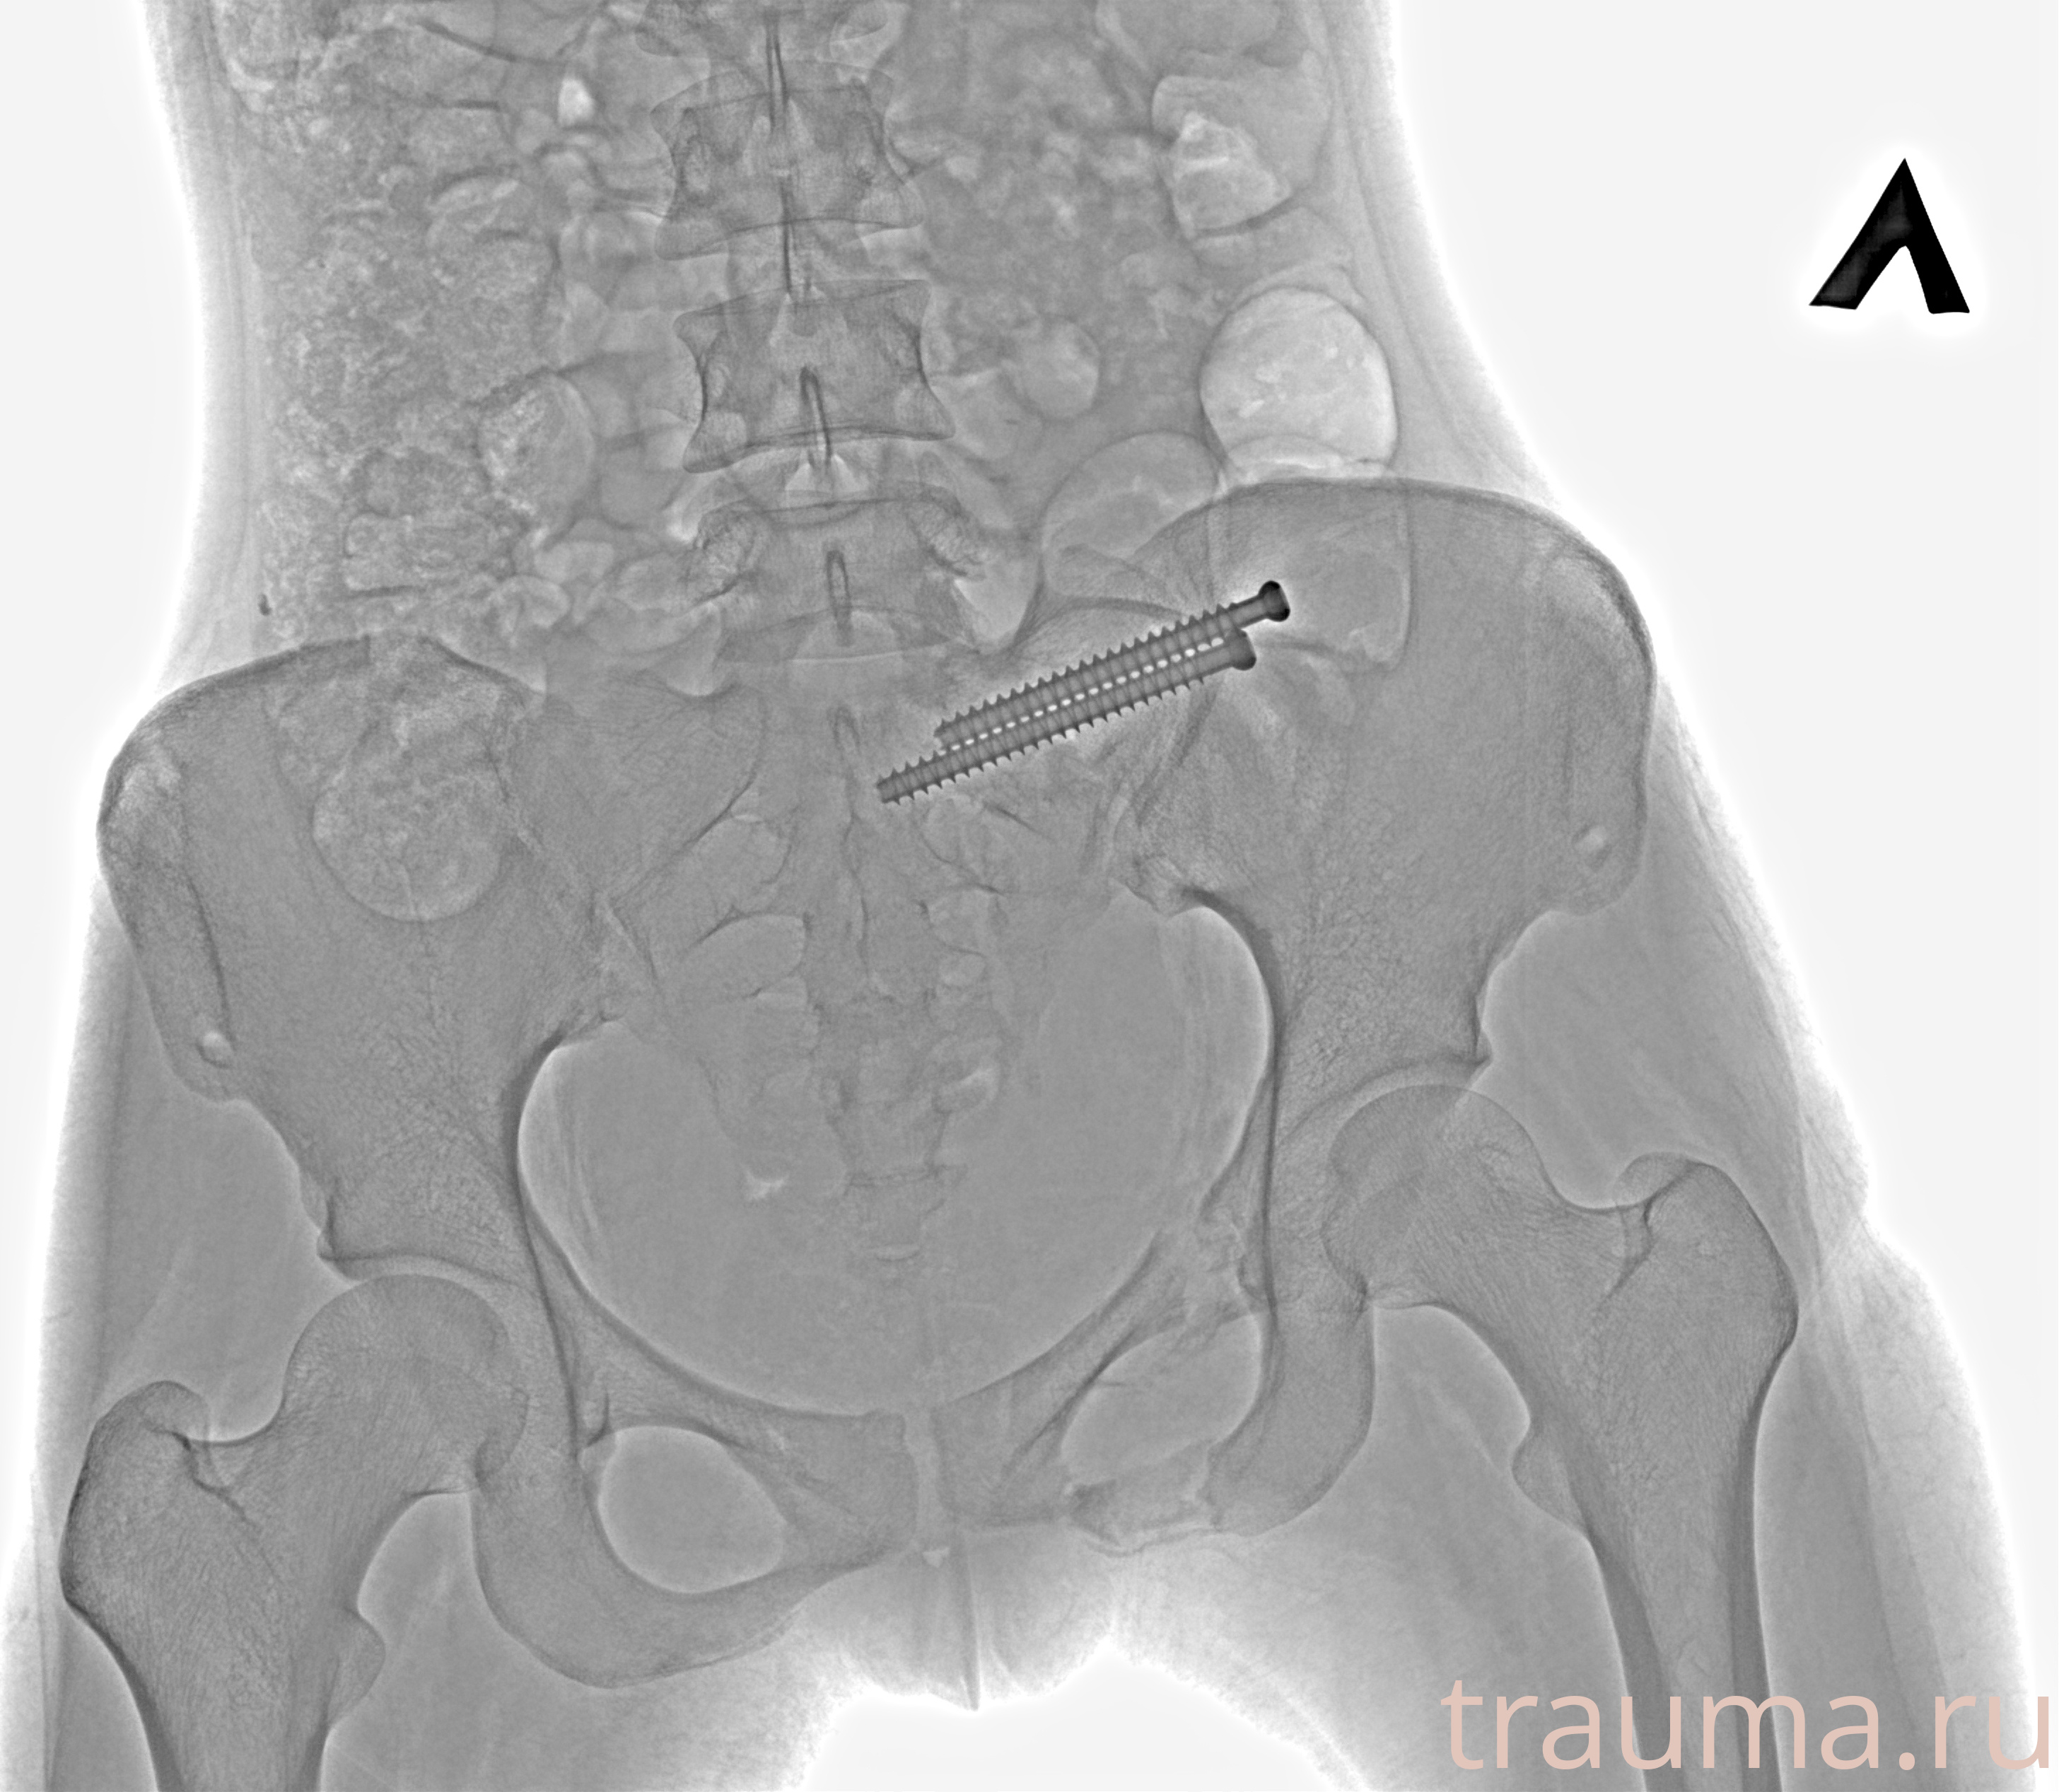

Рентгенограммы